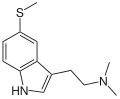

Substituted tryptamines, or serotonin analogues, are organic compounds which may be thought of as being derived from tryptamine itself. The molecular structures of all tryptamines contain an indole ring, joined to an amino (NH2) group via an ethyl (−CH2–CH2−) sidechain. In substituted tryptamines, the indole ring, sidechain, and/or amino group are modified by substituting another group for one of the hydrogen (H) atoms.

| 5-MeS-DMT | artificial | 5-SCH3 | CH3 | CH3 | 5-methylthio-N,N-dimethyltryptamine | 5102-11-4 |